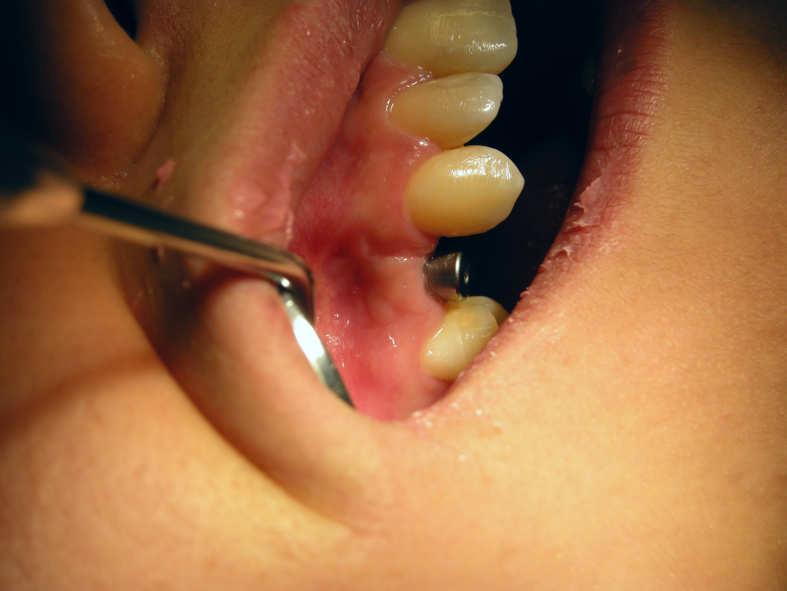

Laser Setting

Diode Laser 810nm

Power: 2.5 Watt,

Pulsed 50 Hz

Fibre 400 micron